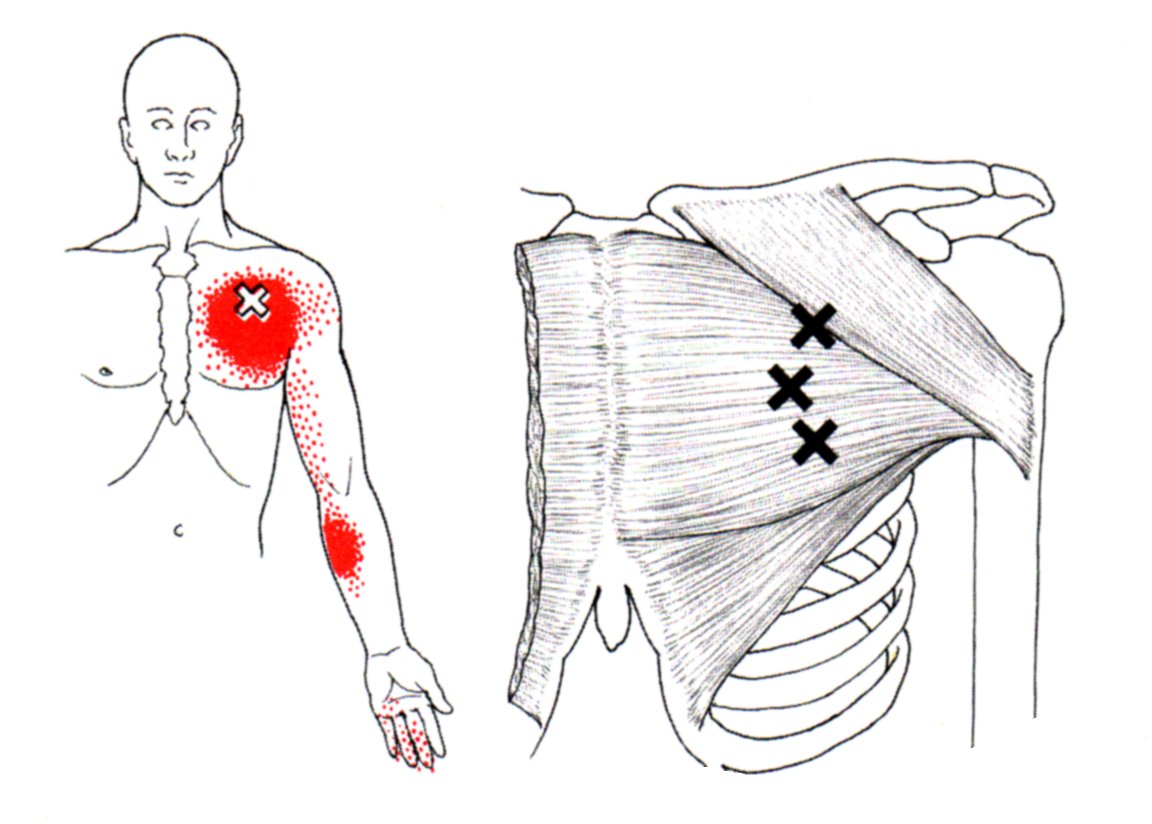

육.트리거 포인트

통증 유발점은 통증과 불편함을 유발하는 근육 긴장 또는 과사용 영역입니다. 대흉근도 예외는 아니며 신체의 다른 부분에 통증을 유발하는 통증유발점을 만들 수 있습니다.

대흉근의 통증유발점은 일반적으로 흉골에 부착되는 근육의 흉골 부분에 있습니다. 이러한 통증유발점은 가슴, 어깨, 팔에 통증과 불편함을 유발할 수 있습니다.

통증 유발점이 대흉근에 있을 때 신체의 다른 곳에서 느낄 수 있는 연관통을 유발합니다. 통증은 어깨, 팔 또는 손으로 퍼질 수 있습니다.

대흉근의 통증유발점은 과도한 사용, 부상, 잘못된 자세 등 다양한 요인으로 인해 발생할 수 있습니다. 통증유발점 마사지, 스트레칭, 근력운동 등으로 치료할 수 있습니다. 더 이상의 통증과 불편함을 유발하지 않도록 대흉근 통증유발점에 대한 치료를 찾는 것이 중요합니다.